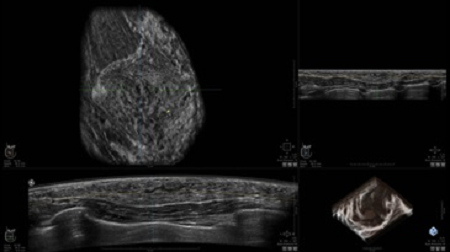

• Получение объемных 3D изображений с возможностью покадрового просмотра

• Получение изображений в поперечной плоскости (в реальном времени) и в коронарной плоскости (статическая, для указания нахождения соска)

• Получение одного объемного изображения менее чем за 60 секунд

• Отображение объемных 3D ультразвуковых изображений, которые состоят из традиционных поперечных и воссозданных коронарных и сагиттальных проекций

• Возможность отображения полного 3D изображения

• Стандартизованная ориентация изображения: «толстый срез» в коронарной плоскости; поперечная; сагиттальная плоскость; радиальный и антирадиальный поворот изображения; просмотр исключительно области интереса

• Инструмент увеличения 4X

• Просмотр кинопетель с регулируемой скоростью воспроизведения